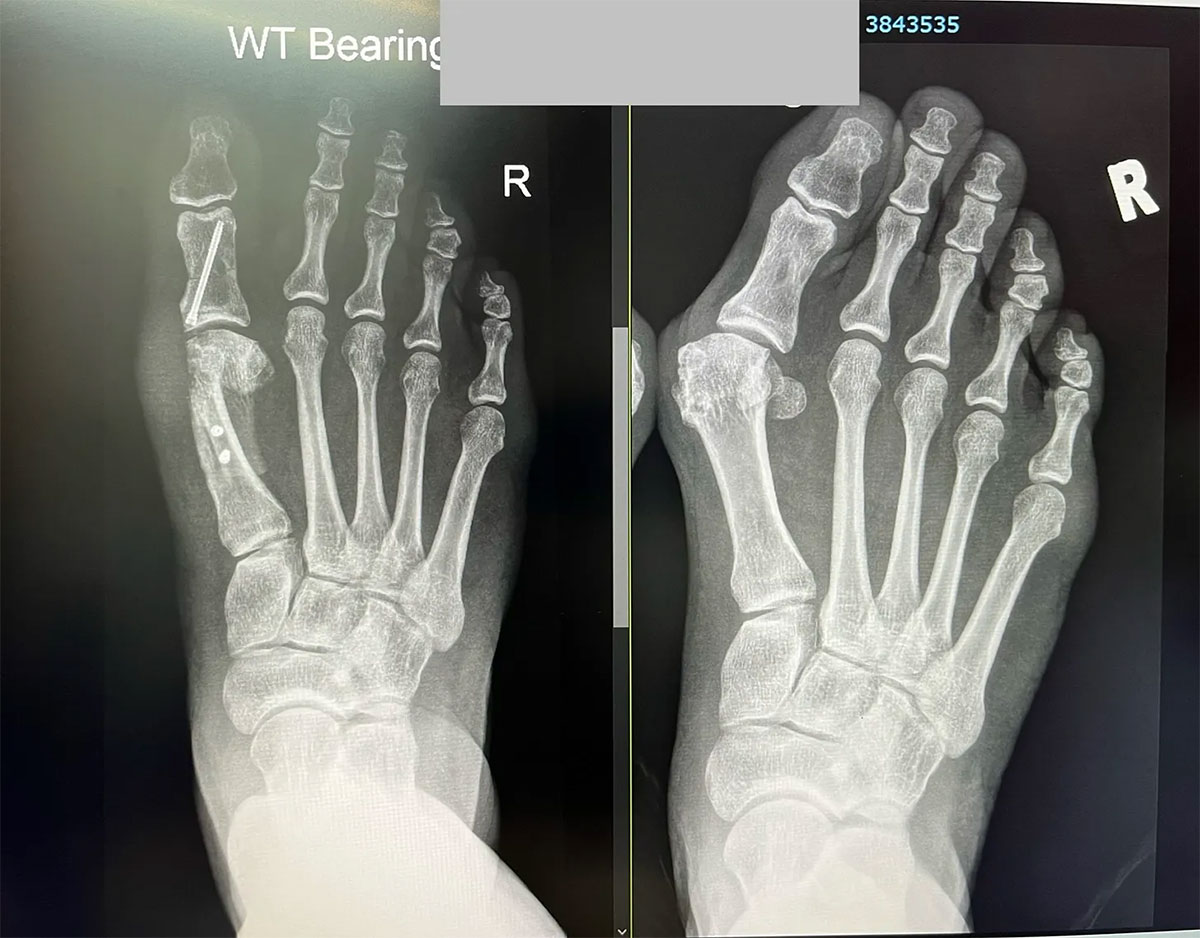

To celebrate her coming of age, we took an X-ray.

A 'before and after' X-ray comparison of a foot that has undergone bunion surgery. The 'before' image on the right shows the severe deformity, and the 'after' image on the left shows the corrected alignment held by surgical pins and screws.

After and Before

Dr Y presided with restrained pride over his baby’s progress. He observed the big toe’s improvement in flexibility and growing strength. He noted that the stent was nicely embedded in place and that there was no pain from it.

Dr Y assured that the continued swelling of the foot was as expected. And that the numbness around the 7cm long scar - where my bunion used to be - was not at all surprising since nerves had been cut and they needed time to reconnect.